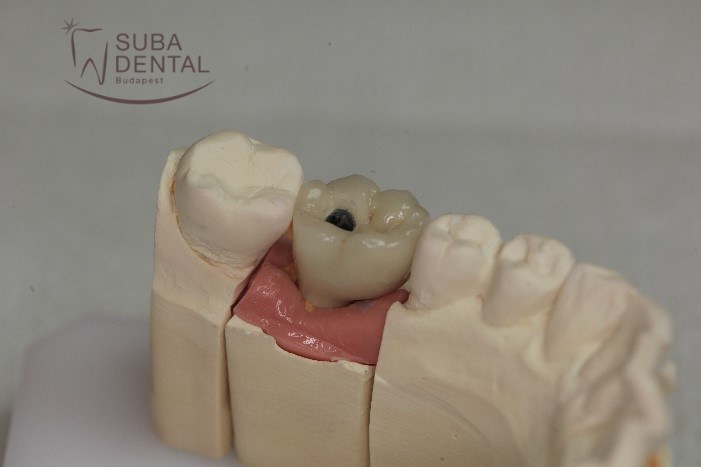

Pour la fabrication de la couronne, nous avons pris des empreintes de précision des mâchoires. Après avoir versé le modèle en plâtre, la morsure de la patiente a été enregistrée par l’instrument Artex, et la couleur de la couronne a été chosie. Avec cette information, le prothésiste dentaire a pu préparer la couronne définitive.

La couronne définitive transvissée sur l’implant sur le modèle en plâtre